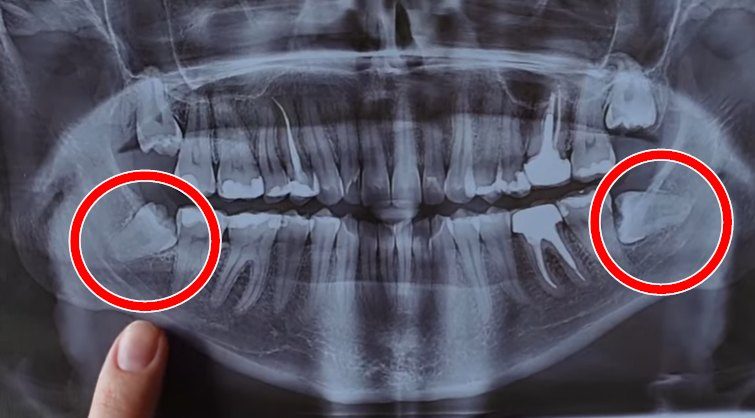

Ретинированный зуб мудрости — это третий моляр (восьмерка), который не прорезался полностью или вовсе не вышел в полость рта и остался в кости либо под слизистой оболочкой. Если объяснять проще, ретинированный зуб — это зуб, который не смог занять свое нормальное положение в зубном ряду.

В современной стоматологии термин «что такое ретинированный зуб» чаще всего используется именно в отношении зубов мудрости, поскольку они прорезываются последними — обычно в возрасте 17–25 лет — и чаще всего сталкиваются с нехваткой места.